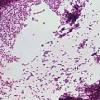

Microscopic Examination Of Listeria Monocytogenes With Gram Stain Of Download Scientific Diagram

Microscopic Examination Of Listeria Monocytogenes With Gram Stain Of Download Scientific Diagram from www.researchgate.net

(applicable to deli ham (25 and 125 g) all listeria spp. Listeria monocytogenes is a bacterium that causes listeriosis, a disease that can have severe consequences for particular groups of the population. Monocytogenes in ovine brain tissue. Listeria monocytogenes in dairy products, seafoods, and meats. Listeria monocytogenes is an important bacterial pathogen in immunosuppressed patients, individuals at the extremes of age including neonates and older adults, pregnant women, and, occasionally, previously healthy individuals. Listeriosis, with a mortality rate of about 24%, is found mainly among pregnant. Beta hemolytic when grown on agar plates. The video below shows these rocket tails in action. A microbial biorealm page on the genus listeria monocytogenes. Gram stain of listeria monocytogenes (source). However, with older cultures the gram stain reaction can be variable and also cells may appear. Listeria monocytogenes gram stain west nile encephalitis creutzfeldt jakob disease haemophilus influenzae type b oral polio vaccine. This pathogen is the only gram positive bacterium that produces endotoxin.

Monocytogenes in ovine brain tissue. Among the six species of listeria, only listeria monocytogenes is the major human pathogen that causes disease in. Try our newest study sets that focus on listeria monocytogenes gram stain to increase your studying efficiency and retention. Natural habitats they are widely distributed in the environment they have been isolated from soil, decaying vegetables, sewage. Listeriosis, with a mortality rate of about 24%, is found mainly among pregnant. Gram stain of listeria monocytogenes (source). Listeria monocytogenes can be found in a variety of dairy products, vegetables, fish, and meat products. However, with older cultures the gram stain reaction can be variable and also cells may appear spheroidal.